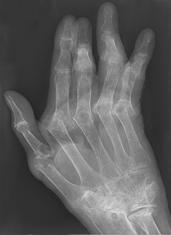

Normal hand bones RA - Damaged hand bones RA - Damaged hand

Description English:

X-ray of right fourth proximal

interphalangeal (PIP) joint with bone erosions by rheumatoid arthritis. Taken October 2002. Same joint is partially healed on a follow-up X-ray

after treatment with conventional disease-modifying

antirheumatic drugs(DMARDs) one year later: File:X-ray of right fourth PIP joint with partially healed bone erosions by

rheumatoid arthritis.jpg